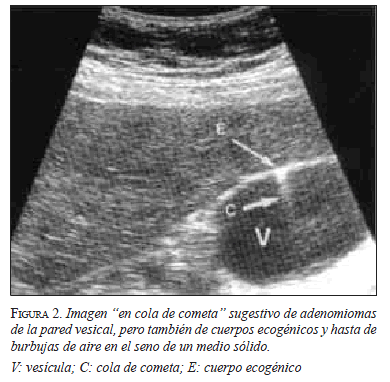

El diagnóstico preoperatorio es difícil y generalmente ambiguo, puesto que en los casos con importante sintomatología siempre se sospechará una lesión maligna que puede someterse a una resección quirúrgica amplia. En la afectación difusa de la vesícula biliar, la ecografía puede revelar engrosamiento de la pared con pequeñas zonas quísticas anecoicas que representan los senos de Rokitansky-Aschoff 17, los cuales pueden contener pequeños cálculos. Un ecografista experimentado podría obtener un alto índice de sospecha de adenomioma, pues este produce un signo radiológico muy sugestivo, denominado "cola de cometa" (figura 2) 8. La forma segmentaria puede confundirse con colecistitis o carcinoma, aunque también es posible la coexistencia de ambas.